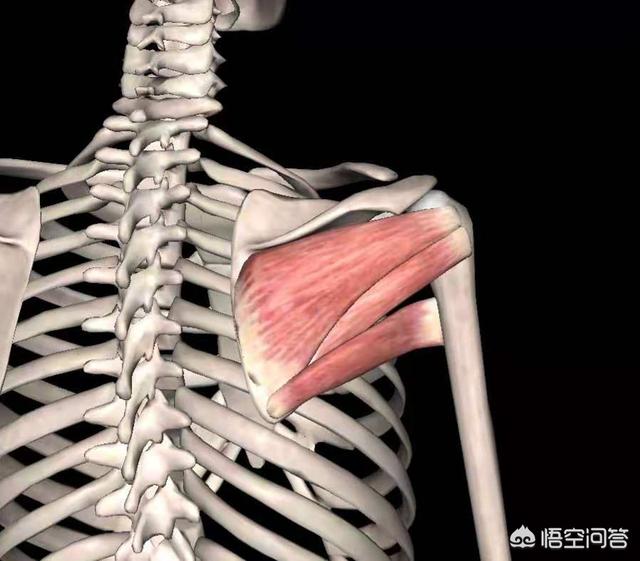

2. les principaux muscles

Les muscles infraspinatus, subscapularis, teres major et teres minor se trouvent tous dans cette zone et peuvent être déterminés par palpation. Les points douloureux trouvés peuvent essentiellement confirmer le diagnostic si la douleur à la pression correspond à la douleur habituelle de l'omoplate.

En ce qui concerne les causes de la douleur, il convient tout d'abord de bien réfléchir si vous avez récemment effectué un travail qui sollicite les muscles. D'une manière générale, étant donné que la région de l'omoplate comporte de nombreux muscles (comme indiqué ci-dessous), les métiers particuliers tels que ceux qui lèvent souvent les bras peuvent provoquer des douleurs à l'arrière de l'omoplate en cas d'accumulation prolongée de la douleur. Cela peut être dû à la sollicitation des groupes musculaires à l'origine de la douleur. Si c'est pour cette raison, il peut être recommandé de se reposer, de se coucher à plat sur le lit, de prendre un sac d'eau chaude pour une compresse chaude (le sac d'eau chaude peut être enveloppé d'une serviette, pour éviter les brûlures), 3 à 5 fois par jour, chaque fois que la compresse chaude dure 20 minutes. Si les symptômes ne peuvent toujours pas être soulagés, il est recommandé de consulter un médecin.